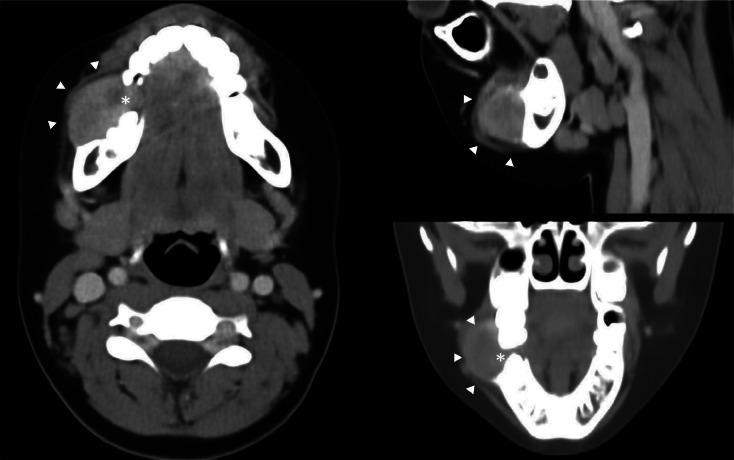

Teaching point: Peripheral giant cell granuloma (PGCG) is a common benign hyperplastic reactive lesion that originates from the soft tissues of the oral cavity and should be considered following a tooth extraction.

Abstract Image